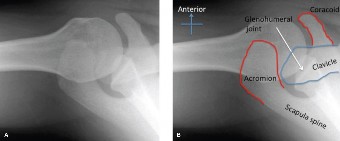

Rotator cuff tears are a common reason for shoulder pain and a common reason to obtain shoulder imaging. As a result, numerous different imaging modalities exist offering different pros and cons. Plain films are still the initial imaging modality of choice. These are most useful in ruling out other possible diagnosis but can help with the diagnosis of a rotator cuff tear as well. Changes to the tendon itself

may appear as calcific tendinosis, which would most commonly be seen at the bone–tendon interface. A decrease in the acromiohumeral distance (less than 2 mm) may also be indicative of a cuff tear. In late cases of rotator cuff tears, superior subluxation of the humerus may be evident. Certain variations in acromial anatomy, including spurs or a hook-shaped (type 3) acromions, may be associated with rotator cuff tears as well. With progression of rotator cuff tears, degenerative changes including spurs, cysts, and sclerosis may be evident at the greater tuberosity. In late, massive tears one may see degenerative changes consistent with rotator cuff arthropathy.

Ultrasound has been gaining popularity recently as it is extremely cost effective when compared to MRI and allows a dynamic assessment of the tendons. It has been shown to have greater than 90% specificity and sensitivity when performed by an experienced operator.

MRI remains the most popular imaging modality for diagnosing rotator cuff tears. Normal rotator cuff tendon appears dark on both T1 and T2 sequences. Tears may be noted as being full-thickness, articular-sided, bursal-sided, or intrasubstance. They are visualized as a disruption in the regular contour of the tendon and increased signal intensity on T2 sequences. Occasionally, an MR arthrogram may provide additional information regarding a cuff tear, although this is not routinely ordered.